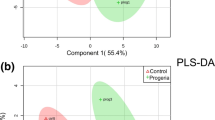

OPLS-DA and volcano map

Through orthogonal projections to latent structures- discriminant analysis (OPLS-DA), we can get more reliable information about the difference between groups. In the figure, horizontal coordinate t [1]P represents the differences between sample groups; vertical coordinate t [1]O represents differences within sample groups. As can be seen from the score chart, the difference is significant, and most samples are in 95% confidence interval (Fig. 1). The volcano map show distribution of metabolites. The card value criteria are based on the following two indicators: P-value < 0.05; VIP>1. Each point represents a peak in the volcano map (Fig. 2).